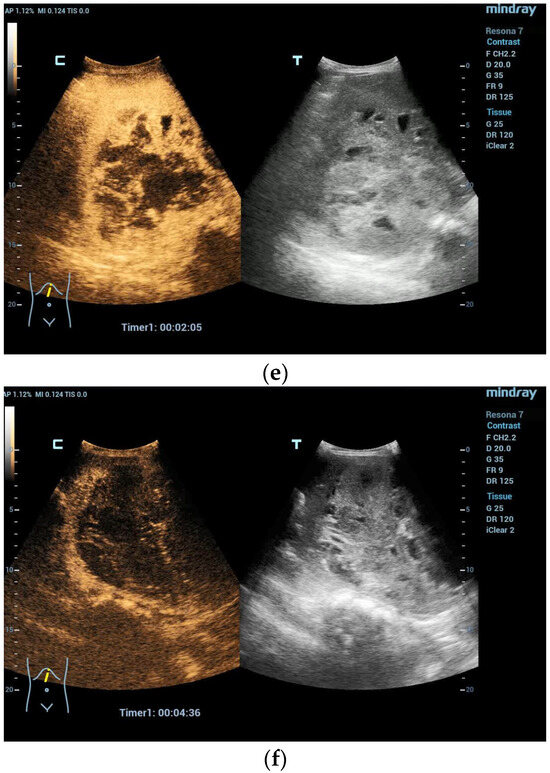

Figure 2.

A 5-year-old boy, presenting with a large mass in the left lobe of the liver. B mode shows a heterogenic mass (a). High resolution B mode with a linear probe clearly reveals multiple cavities representing hemorrhage and necrosis within the mass (b). CEUS in the arterial and early portal venous phases revealed rapid peripheral enhancement with prominent centripetal fill-in and non-enhancing areas (c–e). Late washout after two minutes could be documented (f). Needle biopsy and histological evaluation revealed a highly malignant (G3) liver embryosarcoma.